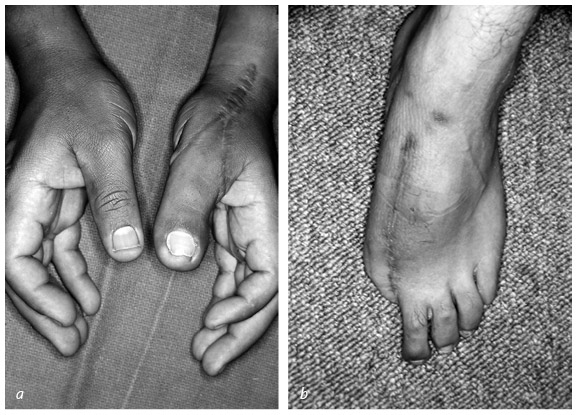

Кистевые хирурги [37] все это знают и при необходимости будут трудиться ночь напролет, лишь бы вернуть поврежденный палец на место. Даже полностью отделенный большой палец можно успешно приживить – реплантировать. Его чувствительность, подвижность и сила никогда полностью не восстановятся, но так, безусловно, лучше, чем вообще без пальца. Если восстановить или приживить эту важнейшую часть кисти невозможно, ее реконструируют. Существует три основные методики, которые я условно называю «упросить», «одолжить» и «украсть». В первом случае хирург и пациент как бы упрашивают обрубок большого пальца вырасти в длину. С обоих концов оставшейся кости хирург вставляет поперечные стальные шпильки, прикрепляет эти шпильки к стальной раме и разрезает кость между ними. Пациент каждый час поворачивает небольшую ручку этого приспособления, напоминающего аппарат Илизарова, и по чуть-чуть увеличивает промежуток между фрагментами кости. Процедура длится от шести до восьми недель. Кость и окружающие ее мышцы, сухожилия, нервы и кожа едва ли понимают, что их растягивают: для них это просто какой-то очень быстрый рост, и им надо успеть. Когда большой палец вновь обретает рабочую длину, хирург заполняет промежуток костным трансплантатом. Преимущество такого способа удлинения в том, что не приходится ничего «одалживать» или «красть». Однако не все так радужно: ноготь и отсутствующие суставы большого пальца уже не вернуть. Другие четыре пальца – указательный, средний, безымянный и мизинец – работают аналогично друг другу, и потеря одного из них имеет гораздо меньшие последствия, чем потеря большого пальца. На этом и основана вторая методика реконструкции большого пальца. Как вы думаете, что приходит в голову хирургу, если незаменимого большого пальца не хватает, а рядом расположились четыре его недостаточно занятых дружка? Разумеется, позаимствовать один из них! Обычно выбирают самый близкий – указательный. Хирург укорачивает его и разворачивает в положение большого. Эта процедура сложнее, чем удлинение остатка пальца, рука становится четырехпалой, зато новый большой палец будет иметь ноготь, и восстановление пройдет быстрее. ![]() ![]() В данном случае культя большого пальца была постепенно увеличена до длины, достаточной, чтобы сжимать и хватать. До лечения большой палец заметно короче – для сравнения стрелкой отмечен первый сустав указательного пальца (a). Во время первой операции врач ставит дистракционное устройство, разрезает кость и осторожно раздвигает ее концы (b). Расстояние между фрагментами кости постепенно увеличивают (на это уходит от шести до восьми недель), наращивают кожу, сухожилия, нервы и кровеносные сосуды (c). После этого в расширенный промежуток кости пересаживают трансплантат из бедра (d). Когда пересаженная кость заживает, работоспособность пальца восстанавливается, и аппарат снимают. Стрелкой показана новая длина по сравнению с исходным состоянием (e) ![]() Реконструкция большого пальца путем укорачивания и разворота указательного пальца: состояние до операции (a) и после нее (b, c) Бывает, что на одной кисти руки не хватает сразу нескольких пальцев или пациенту нужны все пальцы. В этих случаях «пригласить соседа» не получится. Если не удается «уговорить» культю вырасти, хирург может прибегнуть к «краже». Жертвой становится стопа. Большие пальцы ноги по форме почти идентичны своим собратьям на руках, поэтому именно они чаще всего идут в дело – вот только место преступления выглядит довольно неприглядно. Если похитить второй палец ноги, замена из него получится совсем тощая, зато ступня будет иметь аккуратные очертания. Такой вариант обычно выбирают в странах, где в помещении принято снимать обувь. На способность ходить и бегать отсутствие первого или второго пальца ноги почти не влияет. ![]() У этого пациента большим пальцем ноги заменили большой палец левой руки, утраченный в результате травмы. Стопа после операции полностью сохранила функциональность Операция по пересадке пальца с ноги на руку длится от пяти до десяти часов и требует прекрасного владения навыками микрохирургии. Хирург определяет нервы, артерии, вены и сухожилия пальца стопы, изолирует их и отрезает вместе с костью. Ампутированный палец переносят на руку и стыкуют аналогичные ткани между собой. Хирург обычно крепит кость пересаженного пальца к оставшейся в руке кости с помощью стальных штырей. Диаметр кровеносных сосудов – от полутора до трех миллиметров: их необходимо точно соединить практически невидимыми швами, ведь кровь должна двигаться по сосудам, не просачиваясь наружу. Когда кровообращение возобновится, концы кости будут спокойно заживать, не понимая, что стопа перепуталась с кистью руки. Пройдут месяцы, в пересаженный палец врастут новые нервные волокна, и чувствительность восстановится. По-английски получившуюся комбинацию иногда называют thoe [38]. * * * Помните? В период своего зарождения в XVIII веке ортопедия в основном занималась детьми. Доктора лечили деформации скелета, возникшие вследствие перенесенных заболеваний (туберкулеза, полиомиелита и рахита), исключительно неоперативными методами. Со временем эти болезни ушли в прошлое, появилась общая анестезия, возросли требования к стерильности, операции стали значительно безопаснее, а методы лечения усложнились. Один из таких методов – использование аппарата Илизарова для увеличения роста человека. Итальянские хирурги-ортопеды познакомили страны Запада с разработанными Илизаровым методами лечения переломов и начали применять их в борьбе с низкорослостью. Кое-кто считает, что это лишь косметическая процедура. Другие возражают, что она совершенно необходима для общего хорошего самочувствия тех, чей рост явно ниже нормы. Изначально аппараты устанавливали снаружи на обе ноги: большеберцовые кости распиливали посередине, а затем в течение нескольких месяцев растягивали на пять – восемь сантиметров. Следовали месяцы восстановления: удлиненные кости должны стать достаточно прочными, чтобы выдержать массу тела человека. Сегодня пациенты могут выбрать и другой вариант – удлинить бедренные кости. К сожалению, руки после такой процедуры будут выглядеть непропорционально короткими, поэтому некоторые пациенты не останавливаются на достигнутом и удлиняют плечевые кости. Места установки спиц должны быть тщательно очищены и продезинфицированы – через них в кость могут проникнуть кожные инфекции. Если заражение все-таки произошло, необходимо сразу начать агрессивное лечение, в противном случае одна серьезная проблема сменится другой. |